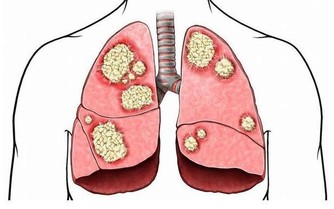

膝關節磨損不可修復

而且,這種對膝蓋的磨損是不可修復的!磨損如果過度嚴重,只能夠置換關節!

一方面我們需要鍛煉大腿和臀部的肌肉群。但是另一方面,我們又不能以傷害膝關節為代價,因為膝關節的壽命由基因決定,是60年,過度使用會加重對它的磨損,並且不可修復。